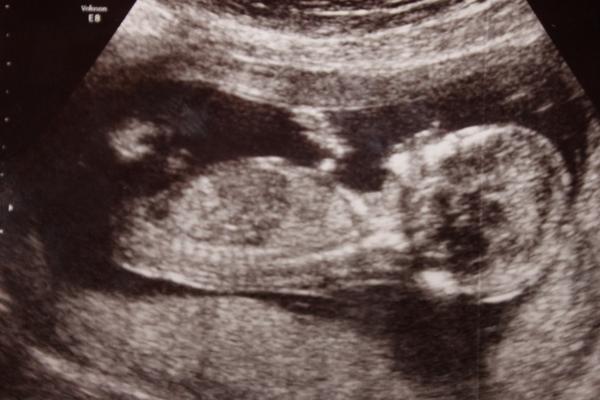

Ahoj, já jsem 13+1tt, Na Veveří v Brně mi na screeningu potvrdili na 90% kluka. Pozná se to prý podle pohlavního hrbolku - podle Dr. klukům vrcholek hrbolku míří víc nahoru k bříšku a holky ho mají protáhlejší směrem dolů k nožkám...Uvidíme, co nám potvrdí příště 🙂 ale já věřila, že je to bude kluk už od oné noci 😀 poprosila jsem o něj 😀 a to překvápko, když mi to potvrdili 😀 MUDr. Doubková umí vše krásně vysvětlit, je precizní a velmi příjemná... 😉

Ahojky, holky, kdyz zkoumali co cekate, tak to bylo asi podrobneji a priblizovali mimise? Mi v patek po dotazu, jedtli jse poznat, mimuse mela z boku celeho a pry ze kluk, byl ta videt jakoby pytlik, ale pochybuju, ze na konci 13 tt by tam byl a tak veliky, spis mi to prislo jako pup. snura.. :( uvidim ve stredu na kontrole, se poptam...